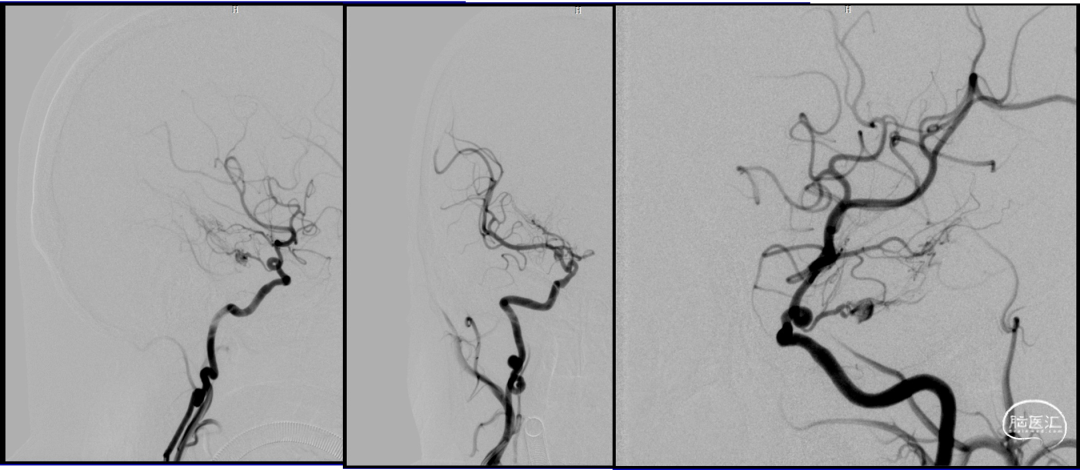

2023-08-30

术后造影:假性动脉瘤消失

后交通动脉在向后稍内行走的过程中发出两组约2 -8条(以4条为多见)细小的中央支(图1)。前组供应丘脑下部、丘脑腹侧部;视束前部和内囊后肢。后组主要供应丘脑底核。这些中央支之间虽然存在吻合,但其中一支阻塞后,因有效的侧支循环难以建立,故多产生相应供应区的梗死。该病例栓塞假性动脉瘤所在中央支没有症状,考虑为假性动脉瘤导致该中央支缺血耐受和血管代偿。